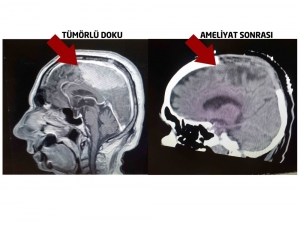

Prof. Dr. Ayhan Okçuoğlu Çavdar’ın Ardından